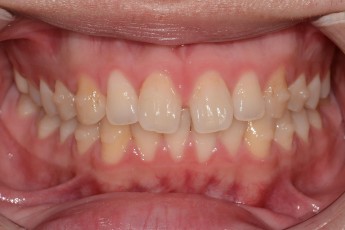

BEFORE & AFTER

- 덧니교정